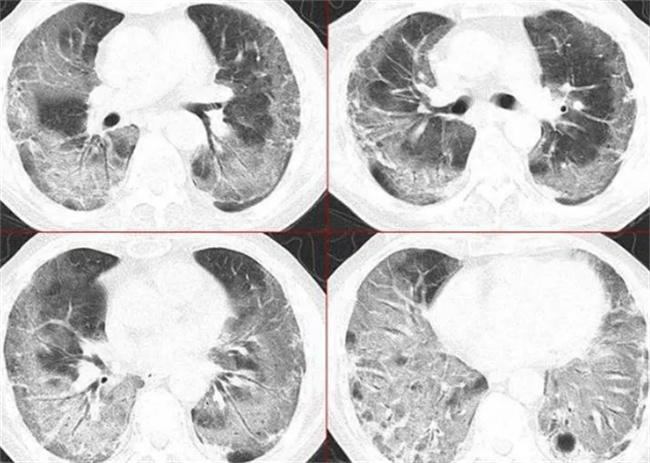

白肺并不是肺部变白,而是影像学上的一个术语。在胸部CT还有胸片拍摄时,肺部的影像学可能会出现黑色,如果颜色变白这就是一种密度变稠的表现。

就是影像学上的一个术语,在拍摄CT之后就会发现肺部影像学主要表现的就是黑色,如果颜色变白,这就意味着密度增稠。大叶性肺炎时还会出现出一种片状变白,会沿着支气管分布。一般在2~3天内就会变成大片的白色状阴影,在临床上会被称之为大白肺,很容易就会引起呼吸衰竭,还有急性呼吸窘迫综合症。

临床上的肺部变白因素比较多,但是在经过分析之后可以看到是两种原因,一种是感染性因素,另外一种是非感染性因素。在大部分的情况下,感染都会有着大量的肺泡水肿,因此肺部就会逐渐的变白。还有一种就是非感染性因素,无论是肺神经源性还是肺源性,又或者是心源性,都有可能会导致肺水肿。在这一个阶段就容易会出现肺部变白,需要注意好一些防护措施。

三、如何确定白肺